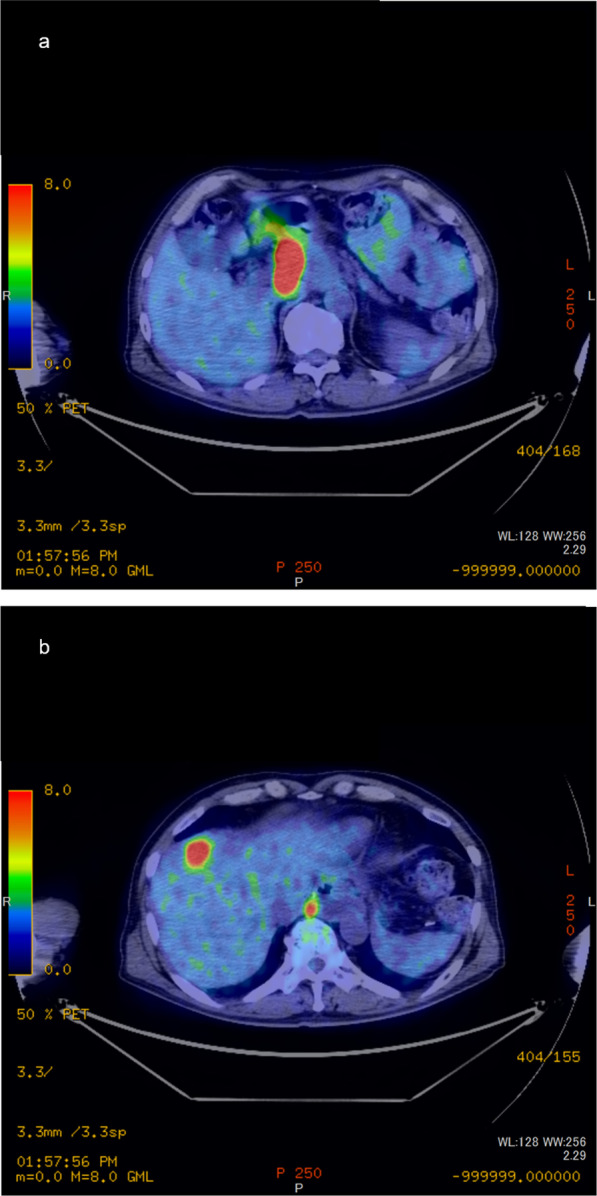

Five months after surgery, a computed tomography (CT) scan revealed a solitary liver metastasis measuring 21 × 15 mm in size in the S4 area (Fig. 1). The surgeons did not judge that the preoperative chemotherapy with CDDP in addition to 5-FU had failed. The patient underwent three courses of chemotherapy with CDDP in addition to 5-FU. During the three courses of chemotherapy, the patient suffered from side effects of chemotherapy including nausea and loss of appetite. Follow-up positron emission tomography PET after the three courses of chemotherapy reveled two new lymph node metastases in the paraaortic area (Fig. 2). The surgeons judged that the first-line chemotherapy had failed because the lymph node metastases showed an increase in size.

Fig. 2.

Positron emission tomography before proton beam therapy. Accumulation of fluorodeoxyglucose is shown in (a) paraaortic lymph node metastasis and (b) liver metastasis in the S4 area with paraaortic lymph node metastasis